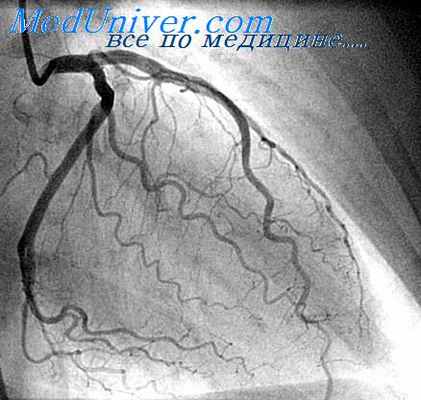

- Ангиография — диагностика атеросклеротического поражения практически любого артериального бассейна, с визуализацией степени стеноза, взаимоотношения артерий с окружающими анатомическим структурами, возможные индивидуальные варианты строения артериального русла. Метод относиться к инвазивным (требующим хирургического вмешательства), назначается по строгим показаниям, когда становиться вопрос о возможной операции.